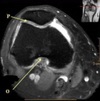

11

What is letter A?

12

What is letter B?

13

What is letter C?

14

What is letter D?

15

16

17

18